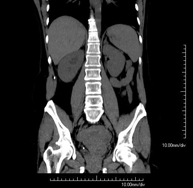

- TC Pelvis Prueba diagnóstica que consiste en obtener imágenes bi y tridimensionales de la pelvis de alta definición anatómica (estructuras óseas, estructuras vasculares, vejiga, útero y ovarios, próstata y vesículas seminales, uréteres, etc.) mediante el empleo de un equipo de TC (Tomografía Computarizada). La mayoría de estudios requieren el empleo de contraste yodado. Prueba diagnóstica que consiste en obtener imágenes bi y tridimensionales de la pelvis de alta definición anatómica (estructuras óseas, estructuras vasculares, vejiga, útero y ovarios, próstata y vesículas seminales, uréteres, etc.) mediante el empleo de un equipo de TC (Tomografía Computarizada). La mayoría de estudios requieren el empleo de contraste yodado.

- TC Abdominopélvico Prueba diagnóstica que consiste en obtener imágenes bi y tridimensionales del abdomen y de la pelvis de alta definición anatómica (estructuras óseas, estructuras vasculares, hígado, páncreas, vesícula biliar, riñones, glándulas suprarrenales, bazo, intestino delgado y grueso, vejiga, útero y ovarios, próstata y vesículas seminales, uréteres, etc.) mediante el empleo de un equipo de TC (Tomografía Computarizada). La mayoría de estudios requieren el empleo de contraste yodado. Prueba diagnóstica que consiste en obtener imágenes bi y tridimensionales del abdomen y de la pelvis de alta definición anatómica (estructuras óseas, estructuras vasculares, hígado, páncreas, vesícula biliar, riñones, glándulas suprarrenales, bazo, intestino delgado y grueso, vejiga, útero y ovarios, próstata y vesículas seminales, uréteres, etc.) mediante el empleo de un equipo de TC (Tomografía Computarizada). La mayoría de estudios requieren el empleo de contraste yodado.

- TC Riñones Prueba diagnóstica que consiste en obtener imágenes bi y tridimensionales del riñón y del sistema urinario de alta definición anatómica mediante el empleo de un equipo de TC (Tomografía Computarizada). Se realiza el estudio antes y después del empleo de contraste yodado en diferentes "fases renales" para una valoración funcional y anatómica (parénquima renal, uréteres, vejiga urinaria, arterias y venas renales, etc.), así como las estructuras adyacentes (vena cava inferior, aorta abdominal, hígado, bazo, etc.). Está especialmente indicado ante la sospecha de lesiones renales, en pacientes con sangre en orina o hematuria, etc. Prueba diagnóstica que consiste en obtener imágenes bi y tridimensionales del riñón y del sistema urinario de alta definición anatómica mediante el empleo de un equipo de TC (Tomografía Computarizada). Se realiza el estudio antes y después del empleo de contraste yodado en diferentes "fases renales" para una valoración funcional y anatómica (parénquima renal, uréteres, vejiga urinaria, arterias y venas renales, etc.), así como las estructuras adyacentes (vena cava inferior, aorta abdominal, hígado, bazo, etc.). Está especialmente indicado ante la sospecha de lesiones renales, en pacientes con sangre en orina o hematuria, etc.

- TC Urológico Prueba diagnóstica que consiste en obtener imágenes bi y tridimensionales del riñón y del sistema urinario de alta definición anatómica mediante el empleo de un equipo de TC (Tomografía Computarizada). Está especialmente indicado en aquellos pacientes en los que se sospecha que hay piedras en el riñón, infecciones urinarias de repetición, etc. El estudio se realiza sin emplear contraste yodado (solo en determinados casos será necesario completar el estudio con contraste yodado). Prueba diagnóstica que consiste en obtener imágenes bi y tridimensionales del riñón y del sistema urinario de alta definición anatómica mediante el empleo de un equipo de TC (Tomografía Computarizada). Está especialmente indicado en aquellos pacientes en los que se sospecha que hay piedras en el riñón, infecciones urinarias de repetición, etc. El estudio se realiza sin emplear contraste yodado (solo en determinados casos será necesario completar el estudio con contraste yodado).